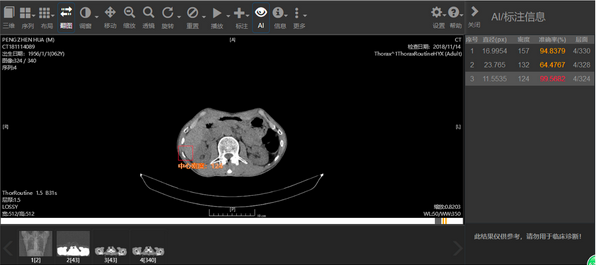

据了解,紛享云影像是以医疗影像智能处理技术为手段,以紛享医疗平台数年积累的海量医疗数据为依托打造的专业医学影像智能处理平台;而移动影像则是在此基础上进行的移动端应用延伸。这两款产品从实用场景层面弥补了诸多现有缺失,可以预见,在未来一段时间,医疗影像AI的应用将迎来大面积的铺开。